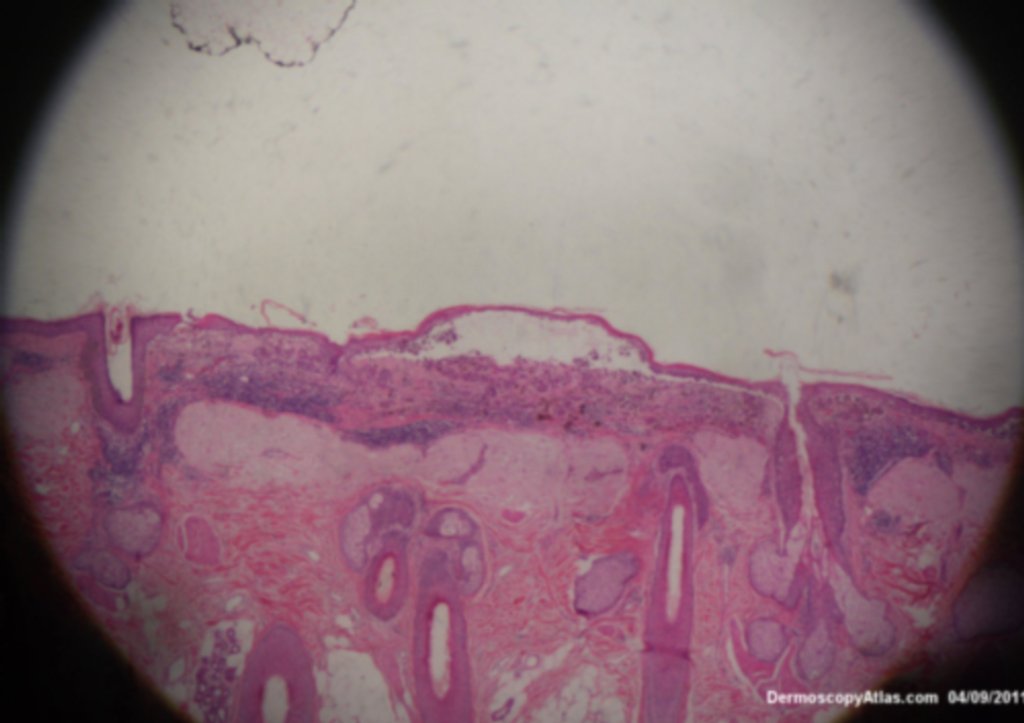

This lesion was noted fotuitously when the patient was having another procedure done on his back. Dermatoscopically it shows peripheral clods of varying sizes, multiple colours and on the enlarged dermatoscopic view some diffuse fine grey dots. It was an invasive melanoma Level 2 , 0.4mm in depth . The histology shows an unusual feature of acantholysis of the tumour nests.